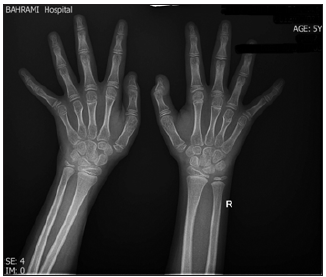

A 5-year-old girl was admitted to the Rheumatology Ward of Bahrami Children’s Hospital affiliated with Tehran University of Medical Sciences with prolonged hallux valgus since one year ago and pain in the first toe (Figure 1). Family and drug history were negative. Her weight and height were 30kg and 135cm, which were above the 95th percentile for age. Physical examination showed generalized hyperpigmentation, hallux valgus, and lateral deviation of hand fingers. The patient was in the pre-pubertal stage .The accelerated growth rate along with skeletal deformity and hyperpigmentation raised suspicion for an endocrine disturbance .Therefore, endocrine consultation was requested to evaluate the adrenal function by measuring ACTH, cortisol, TSH (Thyroid-Stimulating Hormone), and 25 (OH) vitamin D. The cortisol level was lower than normal while the ACTH level was well above the normal limits .Laboratory findings are summarized in Table 1. A hands and feet X-ray showed decreased density of the metacarpal bones as well as lateral deviation of the fingers (bone age=9 years and 6 months) (Figures 2 & 3). Whole exome sequencing revealed homozygous mutation of MC2R gene. The diagnosis was made and she was treated with hydrocortisone [3,4]. She was followed up by a pediatrician and her growth rate, ACTH, and FBS (Fasting Blood Sugar) were observed.

Figure 3: Wrists and hands X-ray of the case.